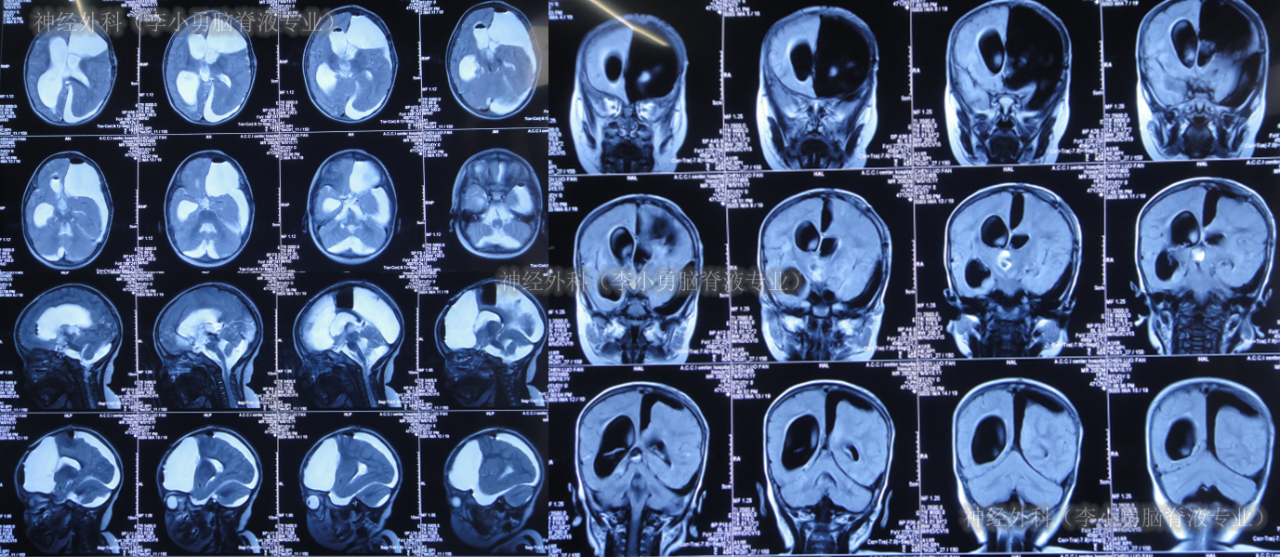

患儿于出生后10月龄即2016年6月1日,患儿意外摔伤头部,在当地的福建省福州市某医院,查头颅CT(图-1)后给予保守治疗后出院观察。

图-1:2016年6月1日头颅CT

但4个月后即2016年10月8日,患儿出现癫痫的症状,第2次就诊于当地的福州市某医院,查头颅核磁(图-2)后诊断为癫痫病灶。

图-2:2016年10月8日头颅核磁

又过5个月,期间患儿癫痫发作变得有所频繁,为求治疗,即2017年3月11日住入北京的某医院,于2017年3月14日,进行了左额颞顶开颅的致痫灶切除术(图-3)。

图-3:2017年3月15日头颅CT

癫痫灶切除术后12天即2017年3月25日,复查头颅CT示癫痫病灶切除术后状态(图-4)。

图-4:2017年3月25日头颅CT

术后24天(2017年4月6日),复查头颅CT(图-5)示“癫痫切除术后现脑积水早期表现”,但未给予处理次日2017年4月7日“出院”。

图-5:2017年4月6日头颅CT